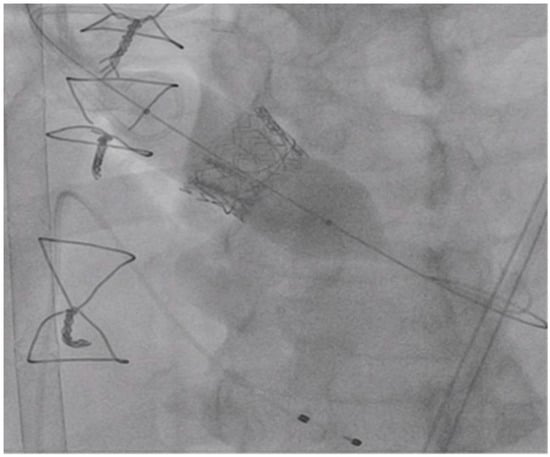

The procedure was performed under general anesthesia, using fluoroscopic and Transesophageal echocardiogram (TEE)guidance. Access for the TandemLife® was obtained in the left common femoral artery and right common femoral vein and both arteriotomy and veinotomy sites were “pre-closed” using two Perclose Proglide (Abbott Inc., Abbott Park, IL, USA) suture mediated vascular closure devices. A 22-French TandemLife® venous cannula in the right common femoral vein, and a 17-French TandemLife® arterial cannulae in the left common femoral artery was placed. The cannulae were then connected to the TandemLife® pump attached to an oxygenator. A cardiopulmonary bypass was initiated at a flow rate of 1.5 to 2 L per minute. Next, a 5 French balloon-tipped transvenous pacer was placed via a 7 French sheath in the left common femoral vein. The transvenous pacer was placed at the apex of the right ventricle, and threshold testing was performed confirming excellent position of pacer and capture. The right common femoral artery was then accessed and “pre-closed” using two Perclose Proglide suture mediated closure devices. A 14 French dry Gore Sheath (Gore Inc., Newark, Delaware, USA) was placed in the right common femoral artery through which a 6 French Judkins Right 4 (JR4) catheter and stiff angled Glidewire (Terumo, Somerset, NJ, USA) was used to cross the aortic valve. The JR4 was exchanged for a 6 French pigtail catheter, through which an Amplatz Super Stiff wire (Boston Scientific, Boston, MA, USA) was advanced into the apex of the left ventricle. The 26 mm Medtronic CoreValve Evolut-R was prepped and loaded onto the back table, if needed. Over the Amplatz Super Stiff wire, a 22 mm True balloon (Bard Inc., Tempe, AZ, USA) was placed in the aortic valve position. Rapid right ventricular pacing was initiated at 180 beats per minute, and the True balloon was inflated up to 12 atmospheres as shown in Figure 2, at which time the Carpentier–Edwards Perimount surgical bioprosthetic valve was fractured.

Figure 2.

Left Anterior Oblique (LAO) Caudal View: True balloon fracturing the surgical bioprosthetic valve. The transvenous pacemaker in place.